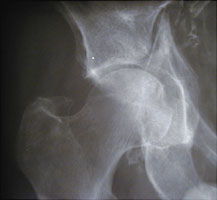

- Click on the image for a larger versionAAP radiograph of the right hip. This shows a markedly comminuted fracture of the acetabulum, involving both the anterior and posterior columns. This patient was the driver of an automobile.